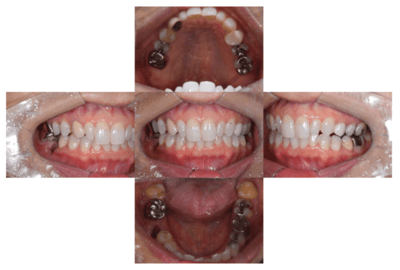

初診時の口腔内

説明:

初診時の口腔内です。かぶせ物があり、一見虫歯とはわからないです。